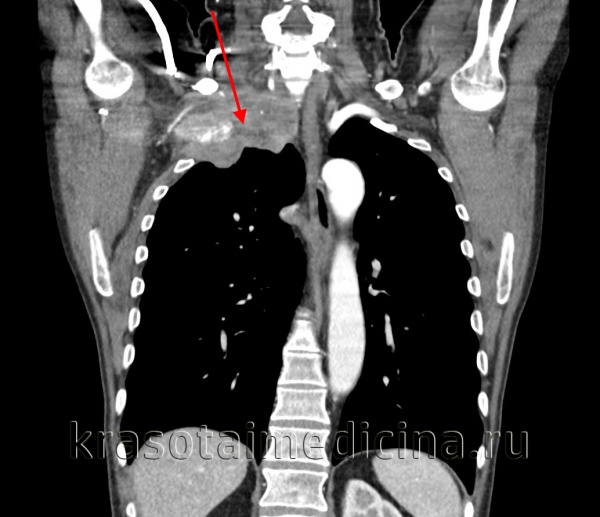

Опухоль Панкоста у мужчины 43 лет. На корональном (а) и сагиттальном (b) срезах видна крупная опухоль верхушки правого легкого, инфильтрирующая средостение и диафрагмальный нерв. О вовлечении диафрагмального нерва в опухолевый процесс говорит высокое стояние купола диафрагмы на стороне поражения. Опухоль имеет широкую поверхность соприкосновения с плеврой.